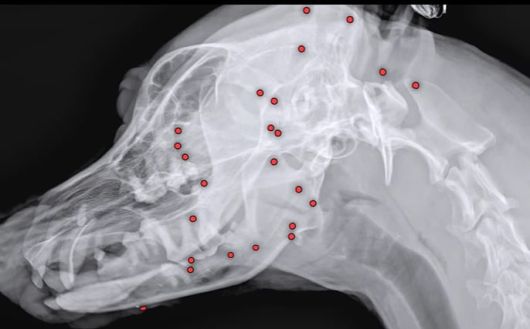

유기견 백구의 몸에 산탄총 파편이 박힌 모습./인스타그램 |

25일 VIP동물의료센터에 따르면 최근 구조된 유기견 백구의 몸에서 70개가 넘는 산탄총 파편이 박혀 있는 것을 발견했다.

구조 당시 백구의 겉모습으로는 총알 자국을 확인하기 어려웠다고 한다. 해외 입양을 앞두고 건강 검진을 위해 X레이 촬영을 했다가 산탄총 파편을 발견했고, 이 때문에 백구의 입양도 불가능해졌다.

동물 병원 측은 곧바로 엑스레이, CT(컴퓨터 단층촬영) 등 정밀 검사에 들어갔다.

안승엽 VIP동물의료센터 원장은 “총알이 머리 쪽부터 어깨, 가슴통, 엉덩이, 다리까지 너무 많이 있었다”며 “살아있는 게 기적”이라고 말했다.

산탄총 파편 제거 수술은 3시간 넘게 진행됐다. 맨눈으로 탄알을 다 확인할 수 없어서 투시기를 이용해 수술 시간이 길어졌다.

안 원장은 “탄알을 한 번에 다 제거하기는 현실적으로 어려워 백구의 얼굴을 위주로 최대한 많이 제거하는 방향을 선택했다”며 총 26개의 파편을 제거했다고 설명했다.